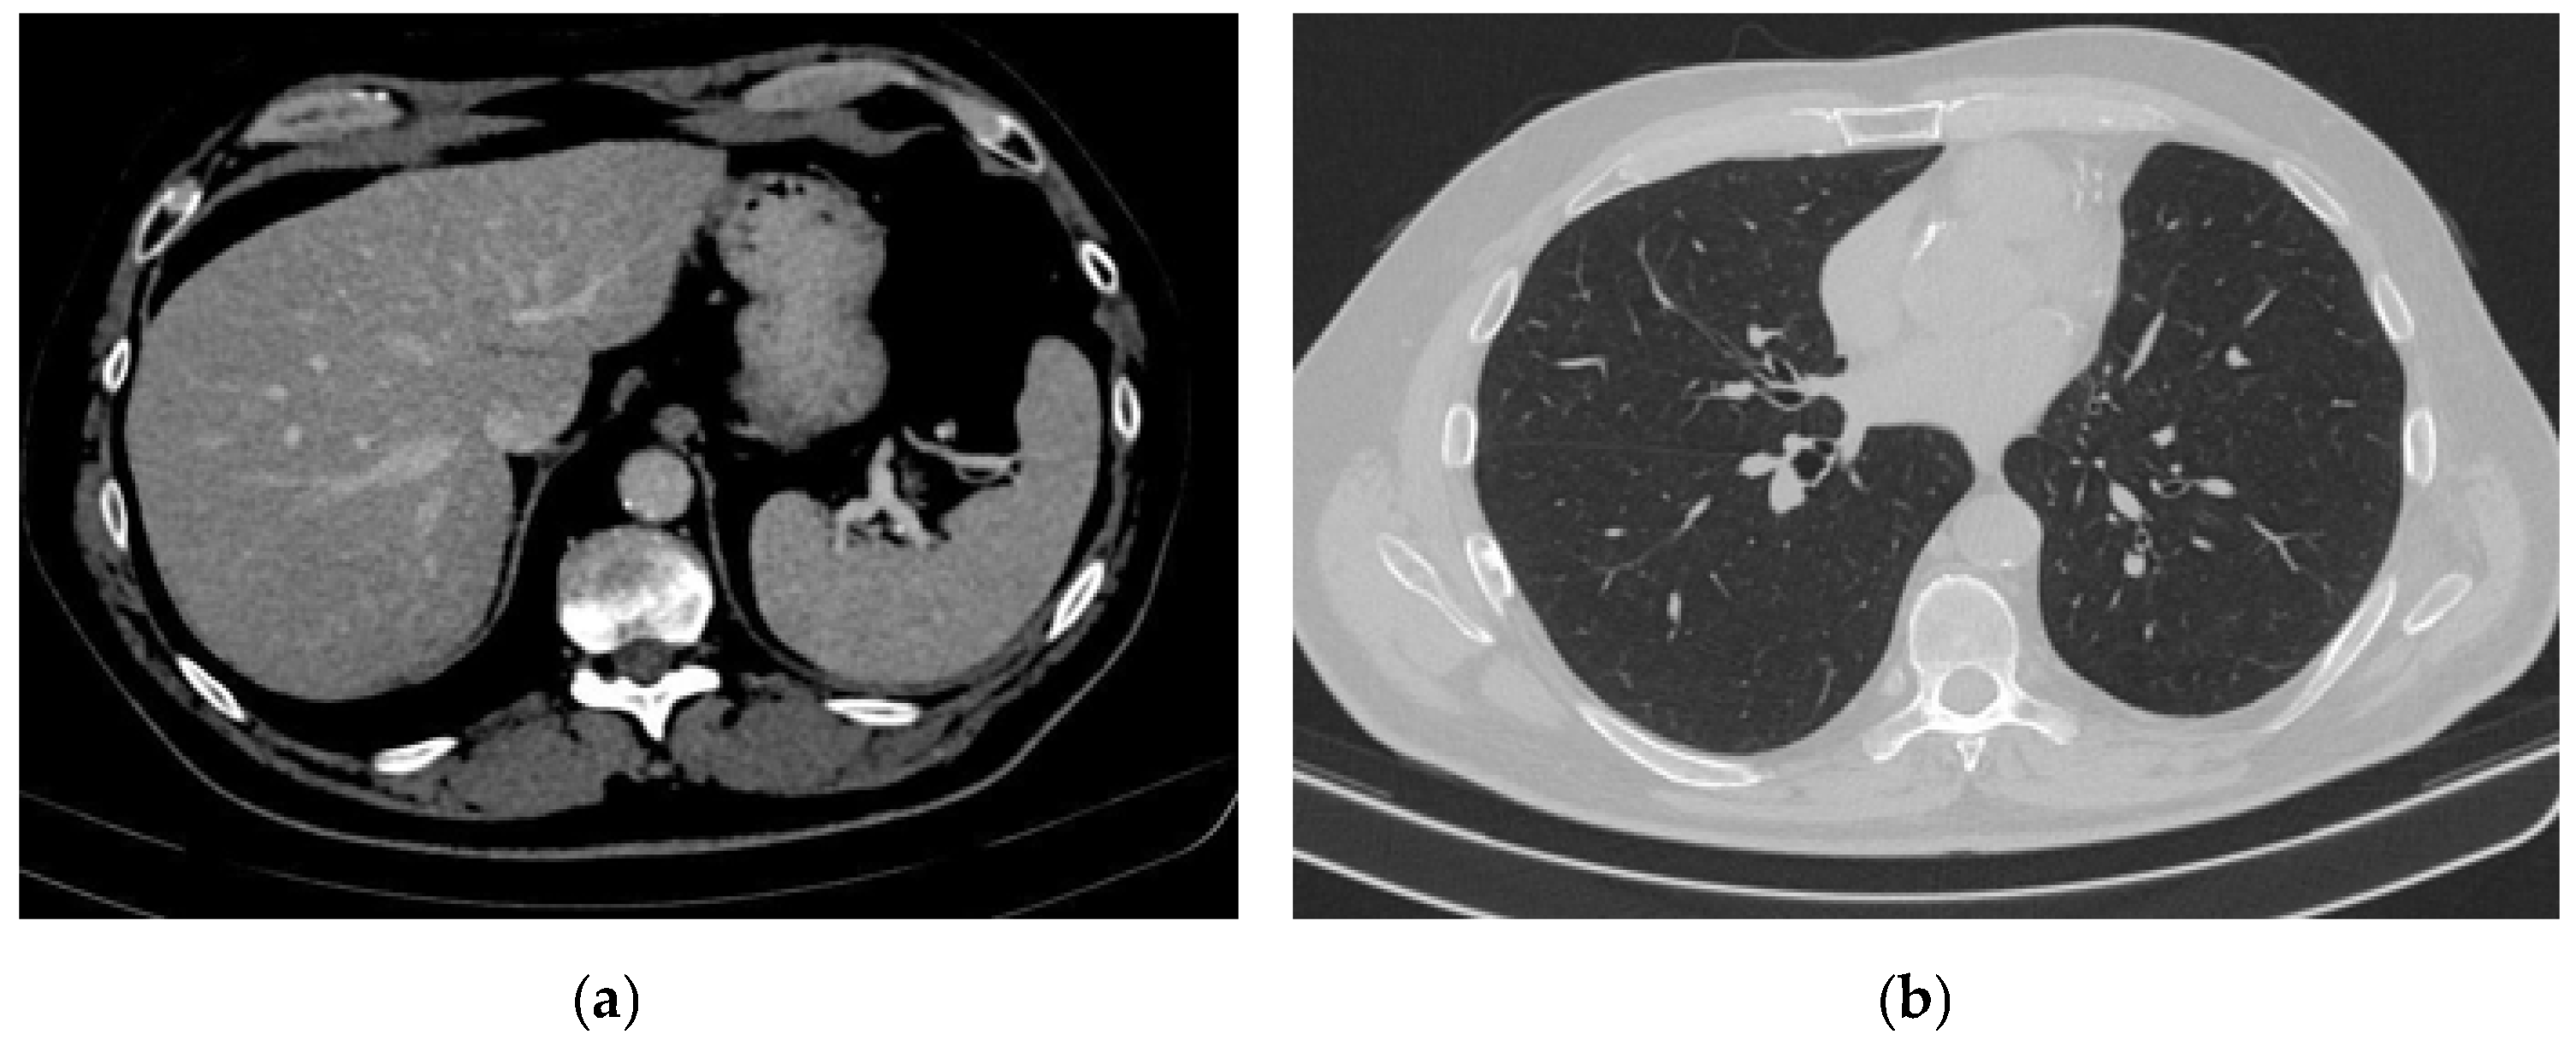

2. Case Presentation